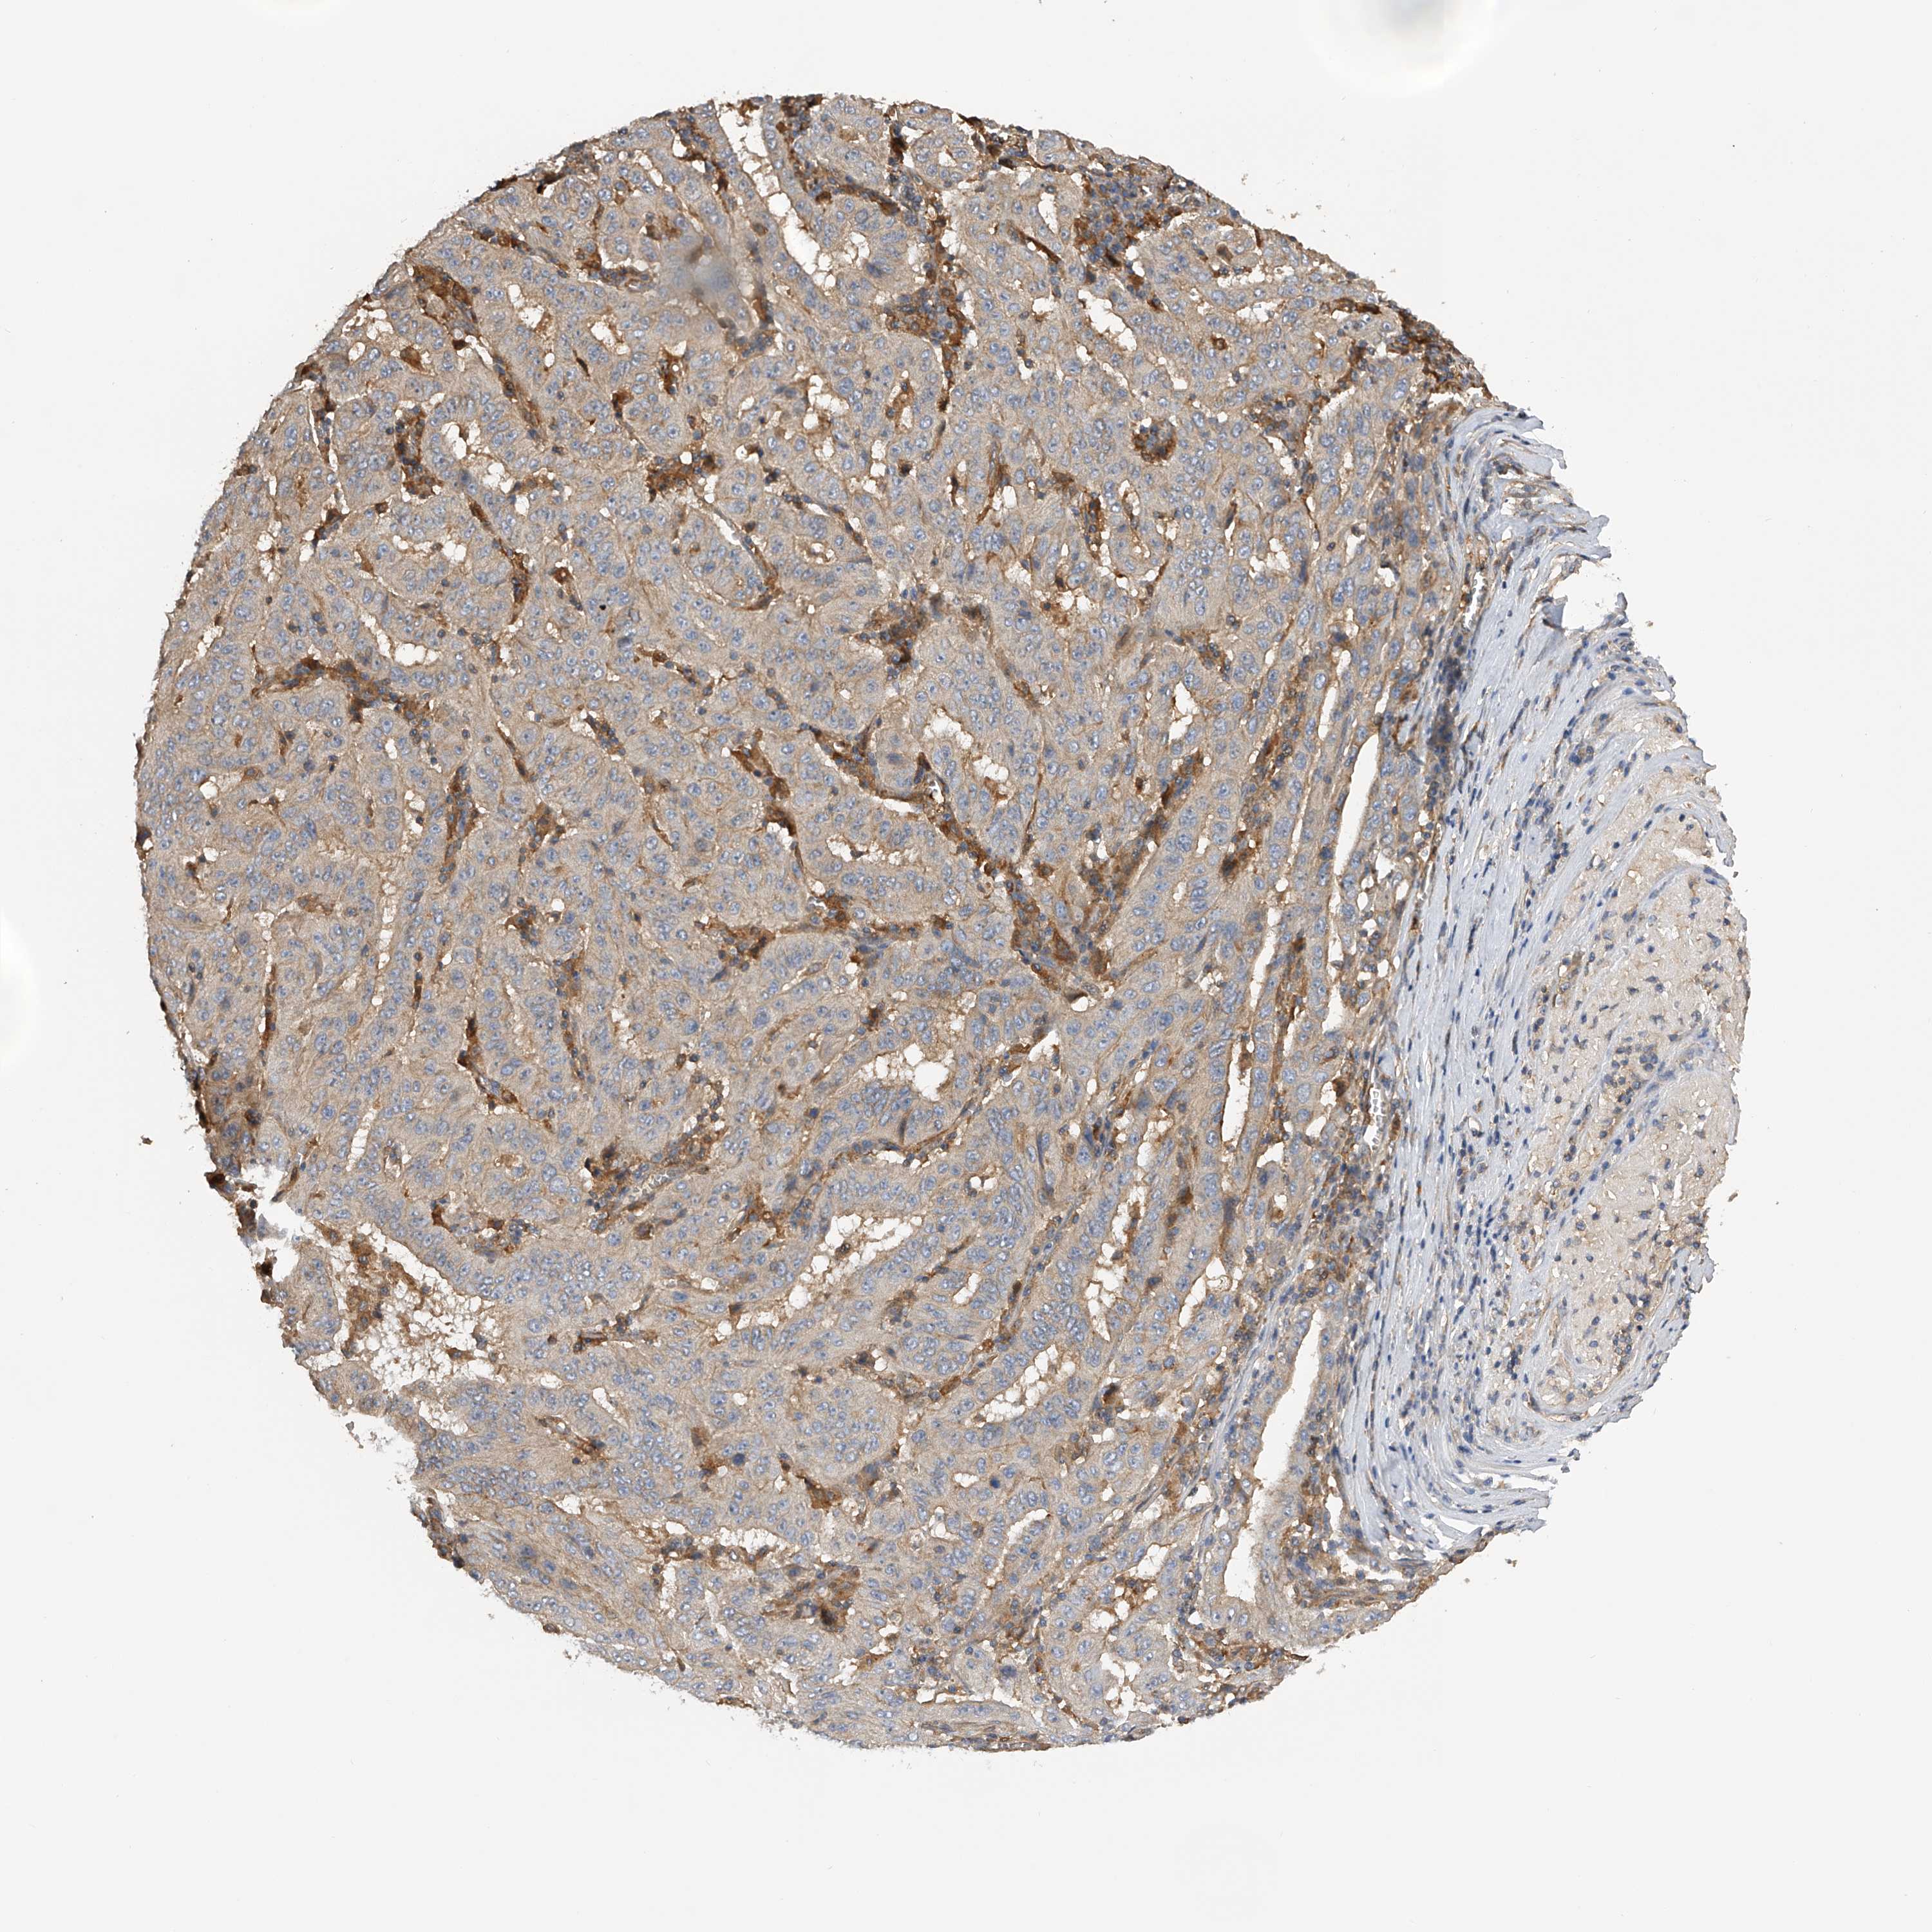

PANCREATIC CANCER - Protein expressioni

A mouse-over function shows sample information and annotation data. Click on an image to view it in a full screen mode. Samples can be filtered based on level of antibody staining by selecting one or several of the following categories: high, medium, low and not detected. The assay and annotation is described here.

Note that samples used for immunohistochemistry by the Human Protein Atlas do not correspond to samples in the TCGA dataset.

Antibody stainingi

Antibody staining in the annotated cell types in the current human tissue is reported as not detected, low, medium, or high, based on conventional immunohistochemistry profiling in selected tissues. This score is based on the combination of the staining intensity and fraction of stained cells.

Each image is clickable and will lead to virtual microscopy that enables deeper exploration of all samples and also displays staining intensity scores, fraction scores and subcellular localization as well as patient and tissue information for each sample.

Antibody HPA029412

Antibody CAB034366

Staining

High

Medium

Low

Not detected

Intensity

Strong

Moderate

Weak

Negative

Quantity

>75%

75%-25%

<25%

None

Location

Nuclear

Cytoplasmic/membranous

Cytoplasmic/membranous,nuclear

Adenocarcinoma, NOS